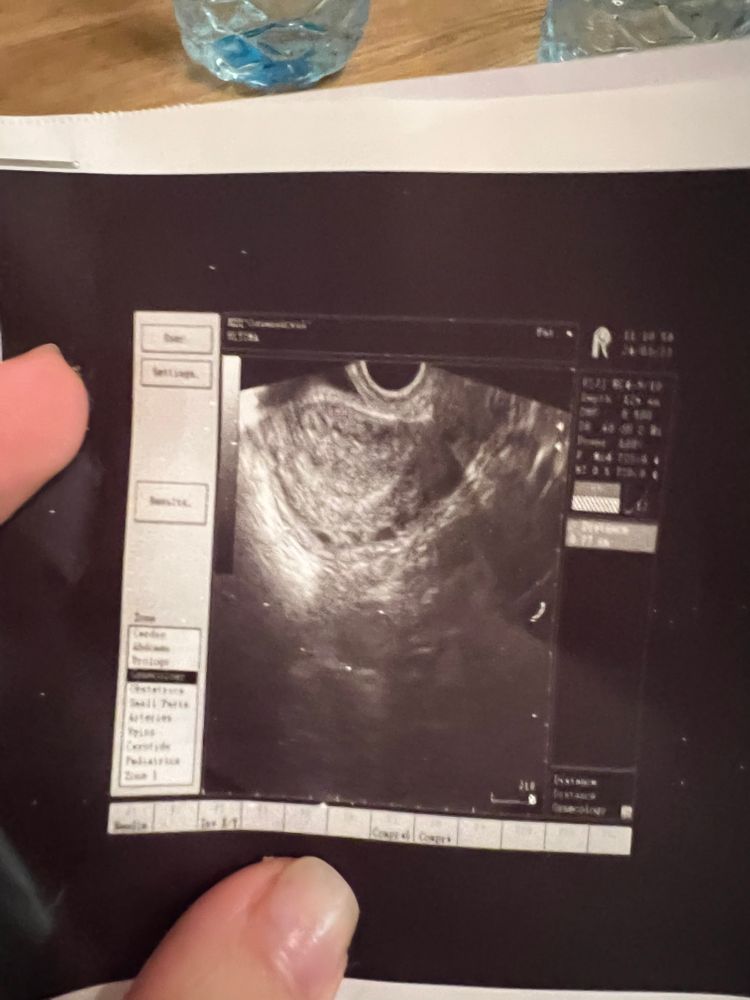

Гинекология (кроме тем беременности)Сегодня была на узи органов малого таза. Ходила не к своему врачу, а рядом с домом клинику. Долго смотрел матку и сказал, что похоже на эндометриоз . Никогда такой диагноз не ставили, на УЗИ ходу часто. Варикоз ставили после первой беременности. Может кто знает похож ли варикоз на эндометриоз и мог ли врач спутать? Я ему сказала про варикоз и он мне сказал , возможно и варикоз🤦♀️ Поссоветовал поставить Мирену в лечебных целях.

Ну хороший узист отличит сосуды от эндометриоза, потому что в них можно посмотреть кровоток) а фото не делали вам ?